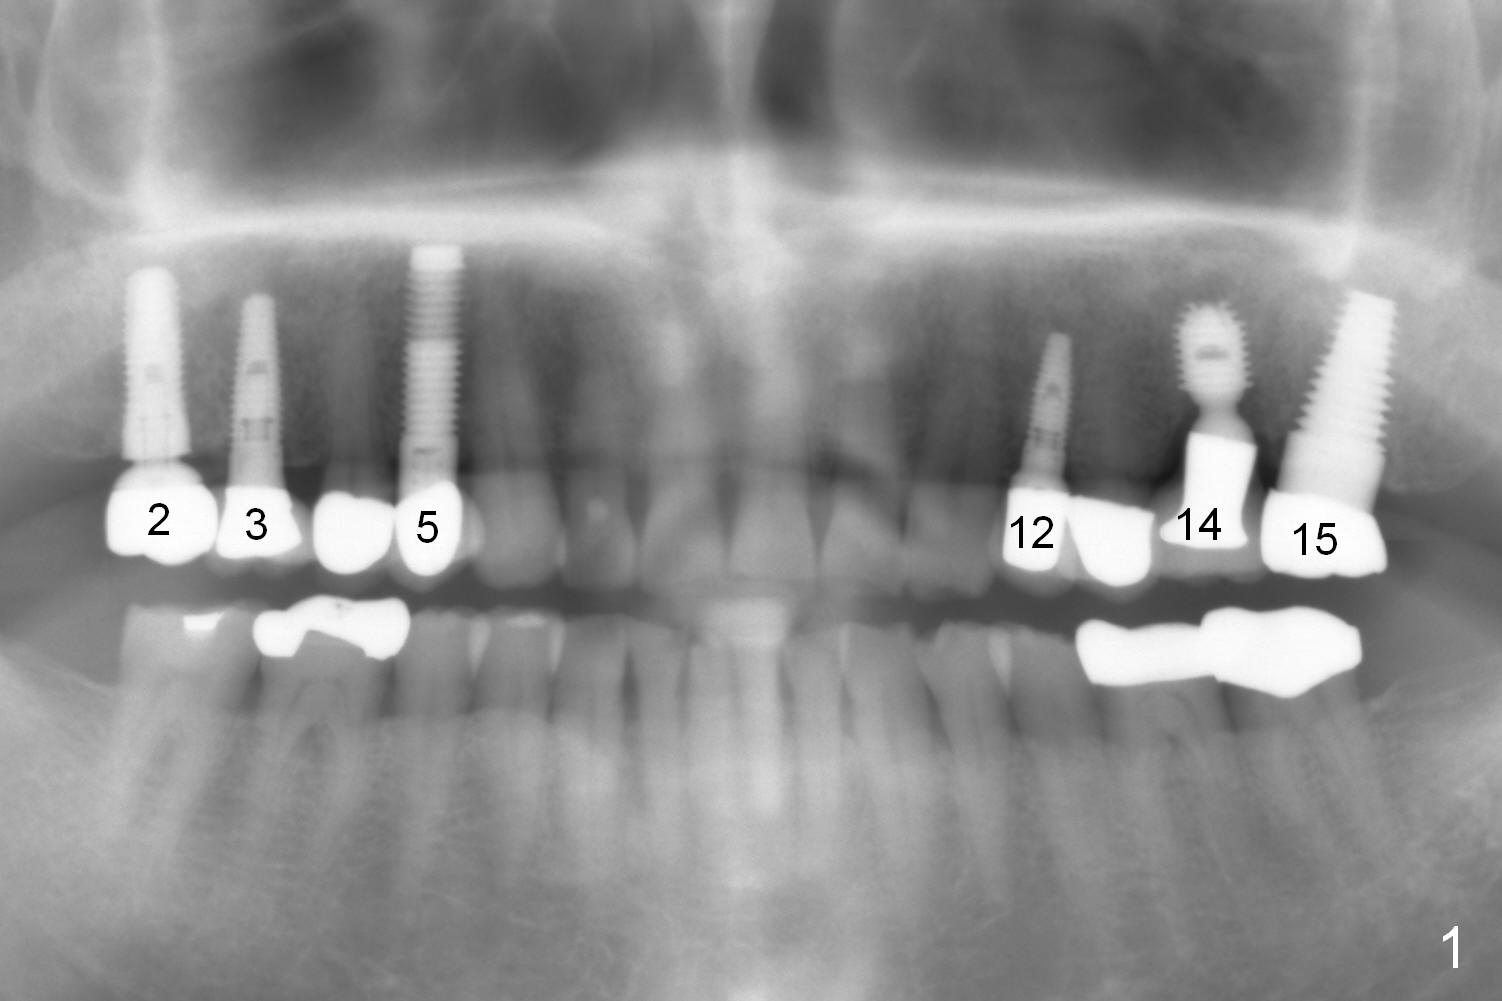

A 73-year-old man returned for recall and had panoramic X-ray taken yesterday. The latter shows no bone loss associated with different types of implants (Fig.1). The implants (relatively small in diameter) and crowns were present at the sites of #3 and 12 when the patient presented to my clinic 6 years ago. His chief complaint was discomfort at #13-15 fixed partial denture (FPD). The tooth #15 seems to be without pathology. To increase its longevity, the FPD was removed (Fig.2), a 5x8 mm Bicon implant (short) was placed at #14 (5 years 11 months post cementation now) and single unit restorations were cemented at #13 and 15 (Fig.3). The occlusal table of the implant crown at #14 is narrow buccopalatally (Fig.4). The occlusal contact of the implant restoration is minimal (Fig.5), which is unfavorable for the weakened tooth (#15). The latter shows sign of failure 7 months post #14 crown cementation (Fig.6 >). The patient refused to accept treatment for #15. Seven months later, the tooth #5 fractured (1st sign of bruxism) and a 5x20 mm cylindrical Tatum tissue-level implant (long) was placed immediately (4 years 5 months in function now). Finally the patient agrees with immediate implant at #15 (7x17 mm tapered Tatum tissue-level implant, large). Follow up is 2 years 7 months post cementation. Ideally 2 implants should have been placed when the FPD was removed. To reduce deleterious effect of bruxism, the last implant was placed with bone expansion at the edentulous area at #2 (5.3x14 mm DIO submerged implant, 1 year 9 months post cementation now). The 2nd sign of bruxism is placement of inlay/onlay on the teeth #19 and 30 (Fig.1). The palatal cusp of the implant crown at #13 remains untreated. The 2 immediate implants at #5 and 15 happen not to have immediate provisional. In all, for a bruxer, an implant does not have to be large or long as long as implant trajectory is correct.